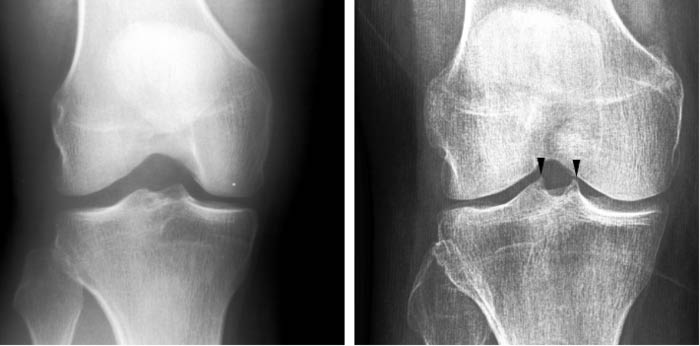

AI tries to detect whether there is spiking on the tibial tubercles in the knee joint, which can be a sign of OA. Image courtesy of University of Jyväskylä.

Researchers from the University of Jyväskylä, Finland, and the Central Finland Health Care District have developed an artificial intelligence (AI)–based neural network to detect early knee osteoarthritis (OA) from x-ray images. The new AI-based method was trained to detect from x-rays whether there is spiking on the tibial tubercles in the knee joint or not. The finding is not at the moment included in the diagnostic criteria, but orthopedic specialists consider it as an early sign of OA.